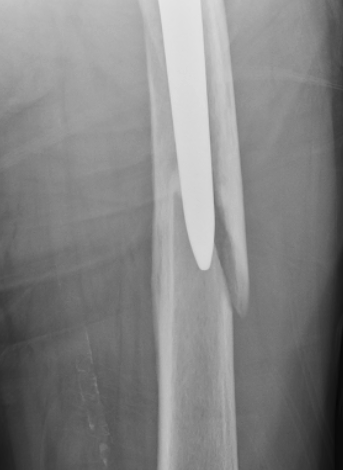

Fracture with stem subsidence around a polished tapered femoral stem treated with ORIF